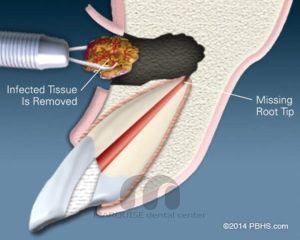

جراحی ریشه دندان

جراحی ریشه دندان در تهران | درمان تخصصی بدون درد در کلینیک مارکیز اگر پس از عصبکشی هنوز درد، عفونت یا التهاب در انتهای ریشه باقی بماند، دندانپزشک با انجام جراحی ریشه (اپیکواکتومی) دندان را نجات میدهد.در کلینیک دندانپزشکی مارکیز تهران، جراحی ریشه با تجهیزات دیجیتال، محیط VIP و بیحسی مدرن بدون درد انجام میشود. اگر ساکن سعادتآباد، شهرک غرب، مرزداران، جنتآباد، گیشا، فرشته، زعفرانیه یا ولنجک هستید، دسترسی سریع و آسان به کلینیک خواهید داشت. جراحی ریشه دندان چیست؟ در این درمان تخصصی، دندانپزشک انتهای ریشه عفونی را خارج میکند و ناحیه را بهصورت دقیق ضدعفونی و مهر و موم میکند.این روش زمانی انجام میشود که درمان عصبکشی بهتنهایی نتواند عفونت را کنترل کند. هدف اصلی:✔ حفظ دندان طبیعی✔